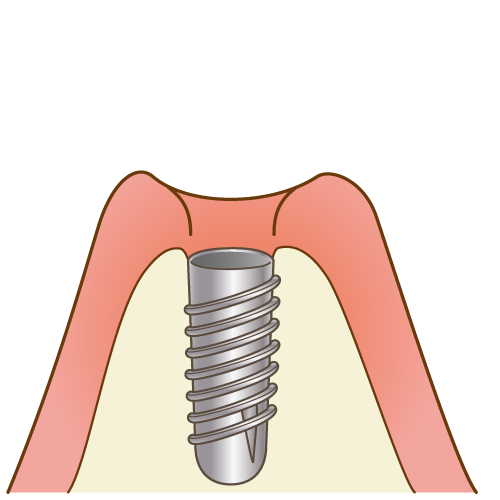

一次手術では、顎の骨に人工歯根を埋め込みます。

一次手術では、顎の骨に人工歯根を埋め込みます。

人工歯根と顎の骨が結合するまで、当院で採用しているインプラントではおおよそ2~3ヶ月ほど待ちます。

人工歯根と顎の骨が結合するまで、当院で採用しているインプラントではおおよそ2~3ヶ月ほど待ちます。

この期間にインプラントと骨はオッセオインテグレーション(骨癒合)という強固な結合を得ます。